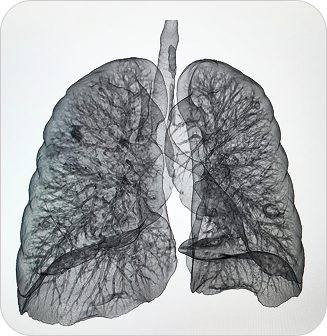

Resonancia Magnética Total

La resonancia de cuerpo entero permite examinar de forma integral todos los órganos y sistemas, sin utilizar radiación, siendo ideal para chequeos médicos preventivos y evaluación de enfermedades sistémicas.

Es un estudio no invasivo que permite visualizar de manera integral el cuerpo humano, sin radiación. Ofrece imágenes de alta resolución de órganos, tejidos blandos, sistema musculoesquelético y más.

¿PARA QUE SE UTILIZA?

- Detección precoz de tumores, lesiones o inflamaciones en órganos.

Seguimiento de pacientes oncológicos. - Evaluación del estado general de salud en chequeos preventivos.

Estudio de enfermedades musculares, articulares o neurológicas que afectan varias zonas del cuerpo. - Detección de metástasis o lesiones ocultas.

¿POR QUÉ ES UN ESTUDIO DESTACADO?

- Cobertura completa del cuerpo en una sola sesión.

- Sin uso de radiación.

- Alta sensibilidad para detectar lesiones incluso cuando son pequeñas.

- Muy útil en chequeos médicos de prevención de enfermedades graves.

Resonancia Magnética Total

La resonancia de cuerpo entero permite examinar de forma integral todos los órganos y sistemas, sin utilizar radiación, siendo ideal para chequeos médicos preventivos y evaluación de enfermedades sistémicas.

Es un estudio no invasivo que permite visualizar de manera integral el cuerpo humano, sin radiación. Ofrece imágenes de alta resolución de órganos, tejidos blandos, sistema musculoesquelético y más.

¿PARA QUE SE UTILIZA?

- Detección precoz de tumores, lesiones o inflamaciones en órganos.

Seguimiento de pacientes oncológicos. - Evaluación del estado general de salud en chequeos preventivos.

Estudio de enfermedades musculares, articulares o neurológicas que afectan varias zonas del cuerpo. - Detección de metástasis o lesiones ocultas.

¿POR QUÉ ES UN ESTUDIO DESTACADO?

- Cobertura completa del cuerpo en una sola sesión.

- Sin uso de radiación.

- Alta sensibilidad para detectar lesiones incluso cuando son pequeñas.

- Muy útil en chequeos médicos de prevención de enfermedades graves.